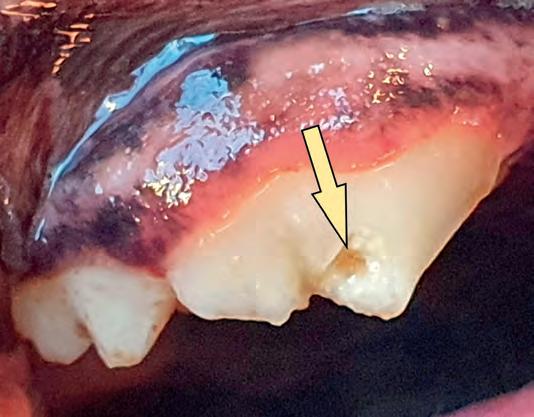

open wortelkanaal altijd zal leiden tot een abces bij de wortelpunt in het kaakbot. Dit zorgt voor veel ongemak bij de hond en een continue infectie in de kaak. Als voorbeeld toon ik enkele foto’s van een patiënt die al enige tijd rondliep met een gecompliceerde fractuur van de knipkies in de bovenkaak.

een kleine ‘chip’-fractuur, zijn de gevolgen groot, want er is sprake van een open wortelkanaal en dus een gecompliceerde fractuur. Bij alle drie de wortels van deze kies (één achterste en twee voorste wortels) zijn abcessen ontstaan in het kaakbot, waarbij de doorgebroken pus uiteindelijk als een grote fluctuerende bal onder het oog te zien en te voelen is (zie foto 3).

Pas na het verwijderen van een dikke laag tandsteen is zichtbaar dat er een stuk van de kies is afgebroken. Hoewel het hier gaat om